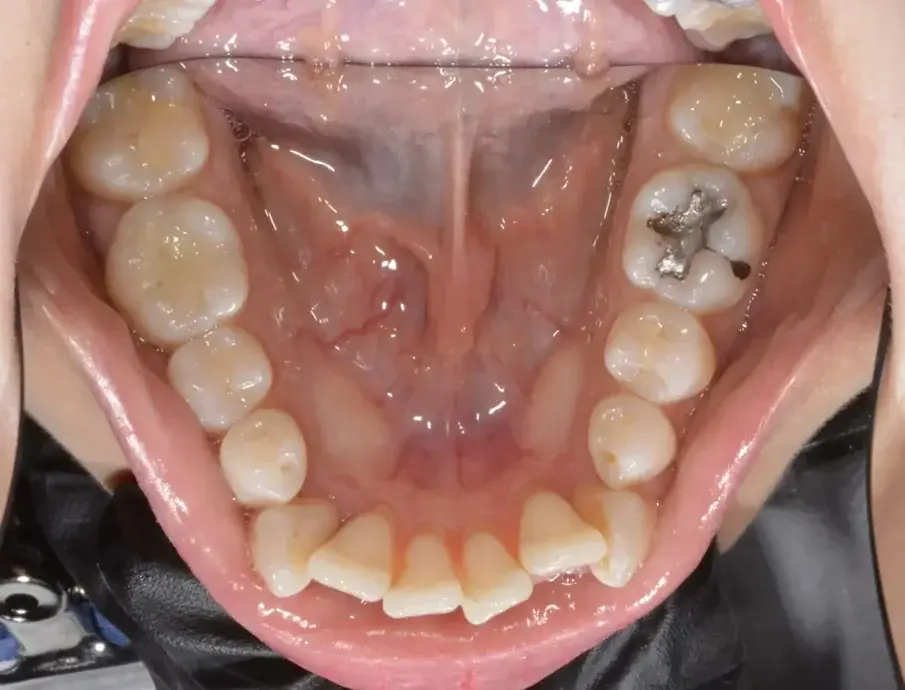

Фиг. 3а: Първоначални оклузални изображения.

Фиг. 3b: Първоначални оклузални изображения.

Фиг. 3c: Първоначални оклузални изображения.